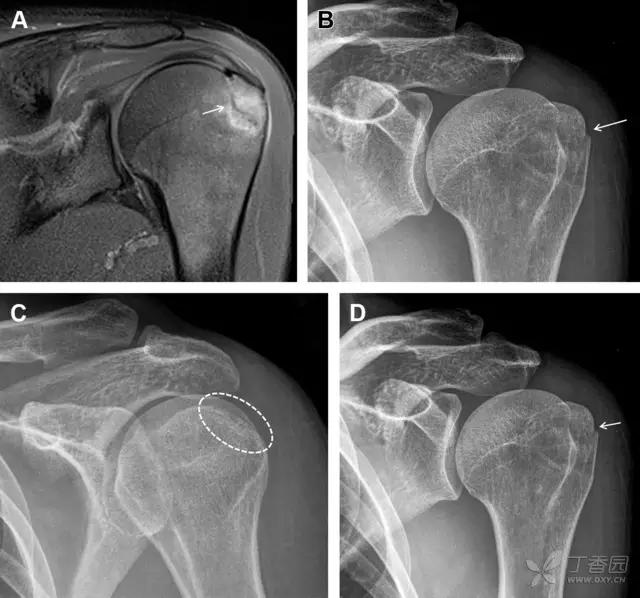

23单纯肱骨大结节骨折

与其它肱骨近端骨折不同,单纯肱骨大结节骨折常发生于年轻人。肱骨大结节骨折常由撞击或剪切/撕脱损伤所致:

撞击包括直接撞击、肩峰撞击、上关节盂撞击(极度外展时);

剪切/撕脱损伤常发生于肩关节前脱位。

在常规前后位片上,大结节与肱骨头重叠,骨折不易发现,外旋位前后位片有助于诊断。

图 1 大结节骨折。(A)脂肪抑制序列斜冠状位 MRI,显示肱骨大结节线性骨折无移位(箭头)与周围骨水肿;(B)外旋位前后位(AP)片,证实大结节骨折(箭头),典型的骨折愈合过程中的骨吸收表现;(C、D)初诊时内旋位、外旋位前后位片,初诊时漏诊,仔细回顾影像,内旋伞下可见双密度影(椭圆),骨皮质中断(箭头)